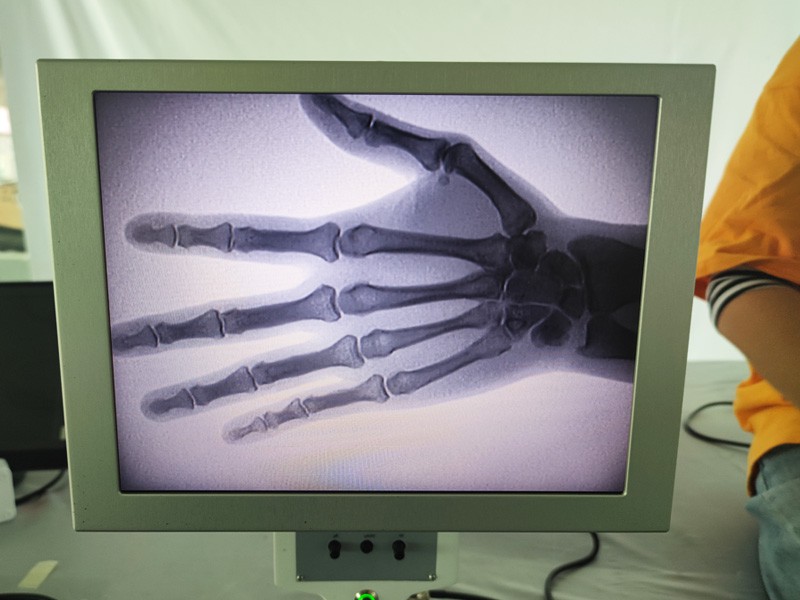

Ас-ц200 преносиви рендген апарат је преносиви инструмент са малом дозом зрачења и веома безбедан. Посебно је погодан за јединице и појединце са недовољним буџетом и ниским захтевима за слике. Нова генерација је опремљена великим екраном високе дефиниције од 10 инча, који има већи опсег перспективе и може у потпуности да посматра цео длан. Углавном је погодан за медицинску ортопедску перспективу. Може се повезати са филмским штампачем за штампање ортопедских филмова, а може се користити и у индустријској производњи и тестирању. Без мрачне коморе, директне перспективе, тренутног посматрања, високе резолуције и јасне слике.

Наш ортопедски рендгенски апарат је висококвалитетан производ који је дизајниран посебно за ортопедско снимање. Може се користити за дијагнозу и планирање лечења различитих ортопедских стања, укључујући фрактуре, дислокације, артритис и туморе костију. Опремљен је напредном рендгенском технологијом која омогућава висококвалитетне слике са смањеном изложеношћу зрачењу. Машина има систем за снимање високе резолуције и може да сними слике било које структуре костију са великом јасноћом.

3. Велики приказ слике: Машина има велики екран слике, који обезбеђује ефикасан радни ток и лаку идентификацију критичних налаза.

1. Дијагноза прелома, дислокација и других повреда костију.